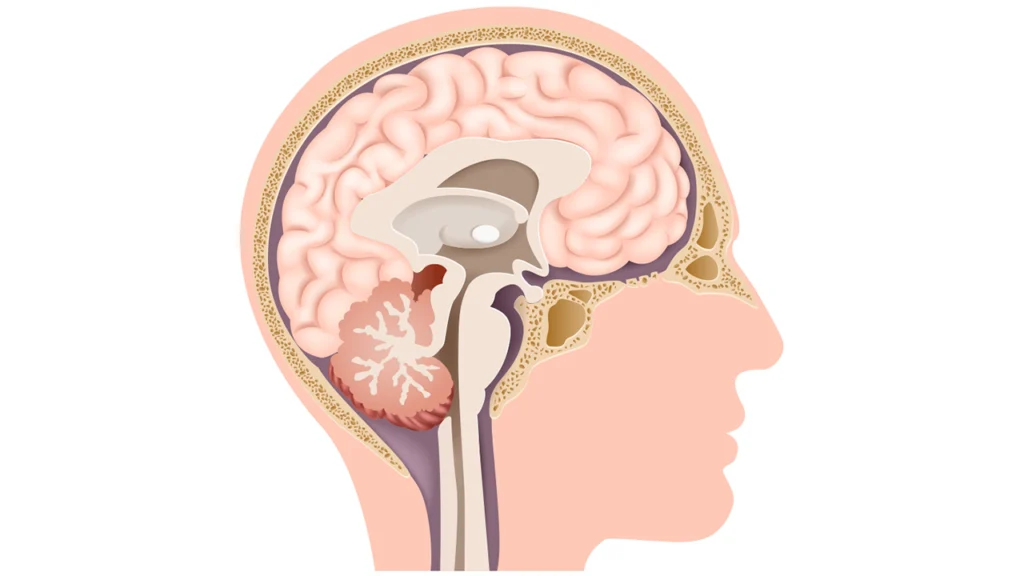

Investigação completa e tratamento preciso para alterações hormonais que afetam o metabolismo e o bem-estar.

Diagnóstico preciso e acompanhamento especializado para condições que afetam o equilíbrio hormonal.

Investigação completa de alterações hormonais que impactam peso, pressão arterial e desenvolvimento.